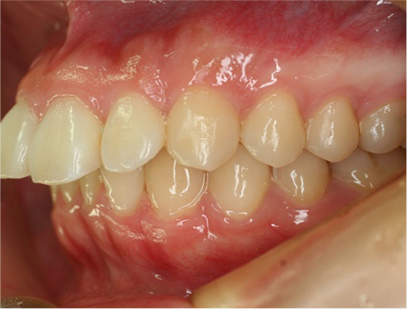

治療後

• 左側

治療前の写真と比べると上下の前歯は後方に下がりました。

そのために、鼻の下の膨らみもすっきりして、下唇も薄くなることができました。

治療期間は2年と6か月を必要としました。